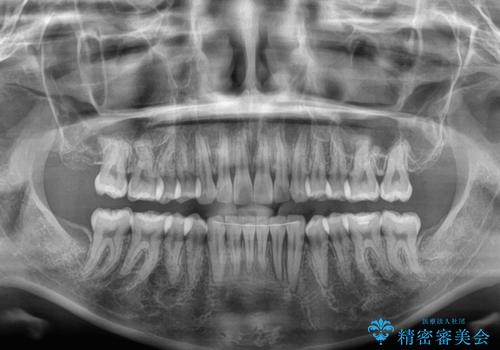

- 上下前歯が非接触となり、前方に突出していることを気にして来院された患者様です。

咬合力が強く、全体的に歯がすり減っているため、インビザライン単独での上顎歯列移動は困難と判断し、補助装置により上顎歯列を後方移動させ、その後インビザラインにて仕上げていくこととしました。

補助装置なしでも改善できる可能性はありましたが、補助装置で確実性を上げ、短期間できっちりと仕上げることができました。